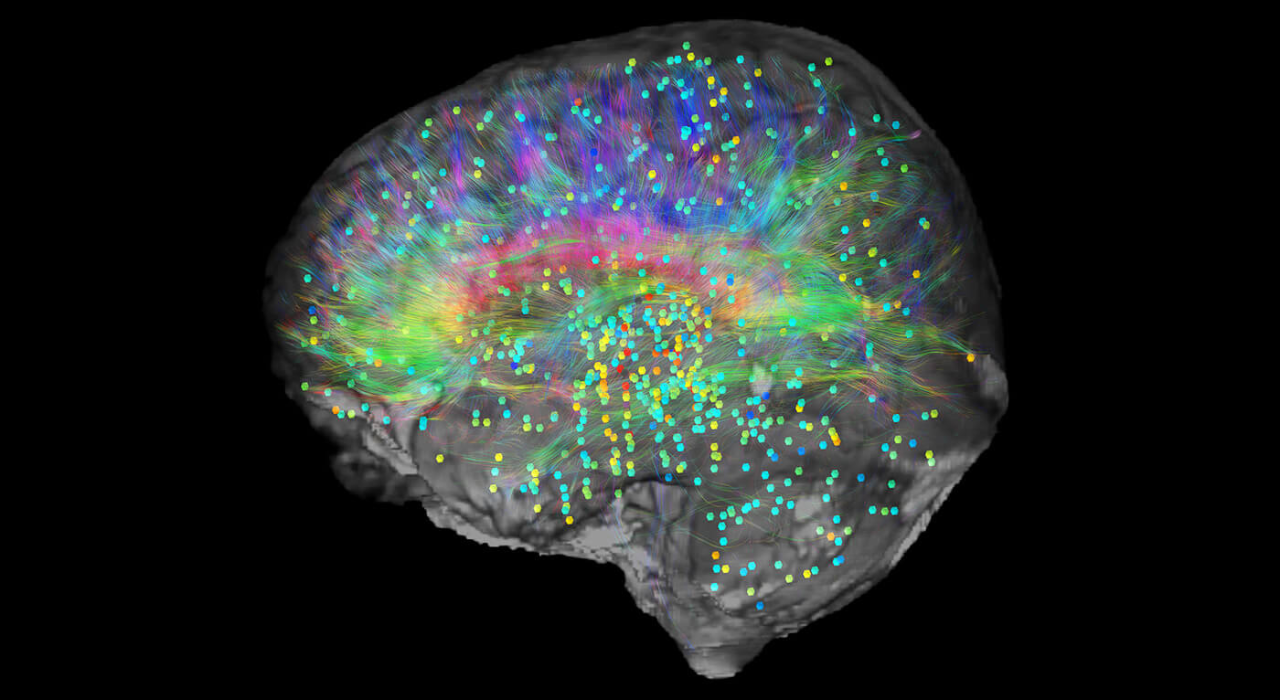

What horror films do to our brains

2025-11-04